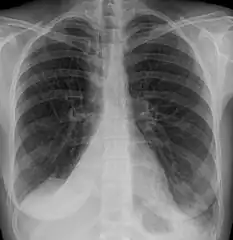

Clinically significant atelectasis is generally visible on chest X-ray; findings can include lung opacification and/or loss of lung volume. Post-surgical atelectasis will be bibasal in pattern. Chest CT or bronchoscopy may be necessary if the cause of atelectasis is not clinically apparent. Direct signs of atelectasis include displacement of interlobar fissures and mobile structures within the thorax, overinflation of the unaffected ipsilateral lobe or contralateral lung, and opacification of the collapsed lobe. In addition to clinically significant findings on chest X-rays, patients may present with indirect signs and symptoms such as elevation of the diaphragm, shifting of the trachea, heart and mediastinum; displacement of the hilus and shifting granulomas.[10]

- Atelectasis of the right lower lobe seen on chest X-ray.